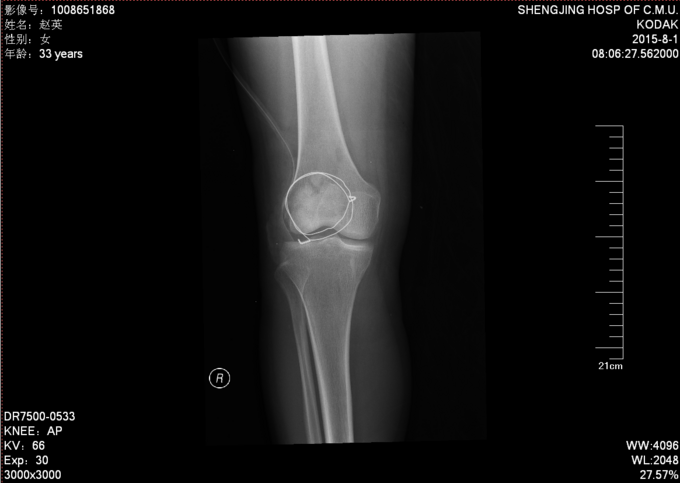

现病史:患者家属代诉于2015年7月23日5点发生车祸,车祸后致右膝部疼痛肿胀活动受限,当时无意识不清,120送至当地医院(辽中县医院),后为进一步治疗,急诊就诊于中国医科大学附属盛京医院,行X线片检查示:右髌骨开放性骨折,急诊给予清创缝合,观察患者病情稳定后,急诊以“右髌骨开放性骨折”为诊断收住我科·。伤来患者无头痛及发热,无咳嗽咳痰,无腹痛及恶心呕吐,饮食睡眠可,大小便正常。

右膝关节已清创缝合,缝合处约10cm不规则创口,右髌骨处软组织肿胀,右膝关节活动受限,右下肢皮肤感觉可,右下肢活动可,。右下肢足背动脉搏动良好,末梢血运良好,皮温正常。

右髌骨开放性骨折 患者急诊行清创缝合后,入院检查后,患者病情平稳,创口1至2天定期换药,观察患者创口愈合,患肢抬高,给予消炎消肿等对症治疗后。入院约一周后创口处无红肿,无渗出,全麻下行右髌骨开放性骨折切口复位张力带内固定术。